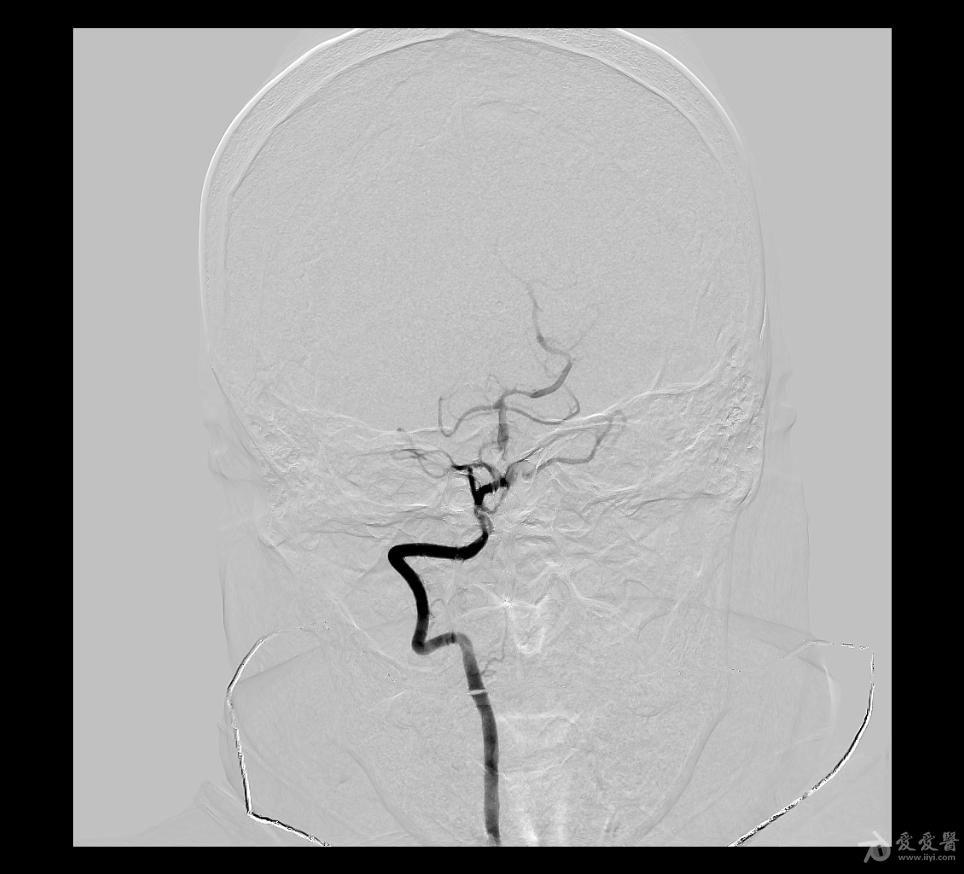

图1:蛛网膜下腔的ct表现图2:cta提示前交通动脉的动脉瘤图3:血管造影